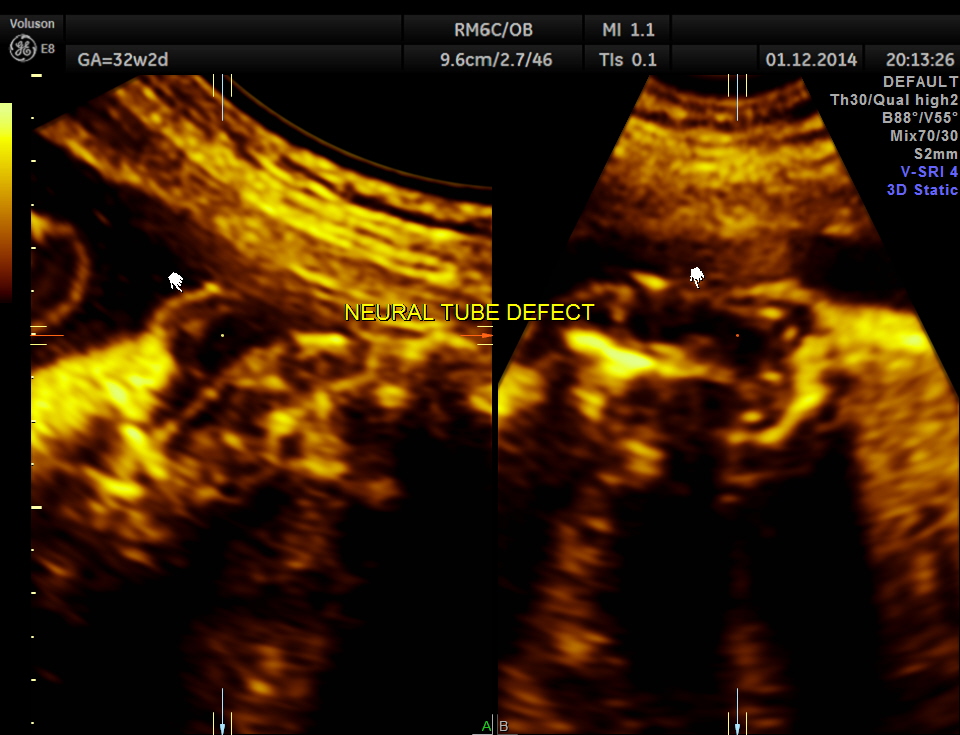

Careful examination revealed a neural tube defect with meningo myelocele at the lumbo sacral level.

Spinal deformity was also noted.

From the ultrasound point of view , we should always look carefully at the spine , in all the cases of hydrocephalus.